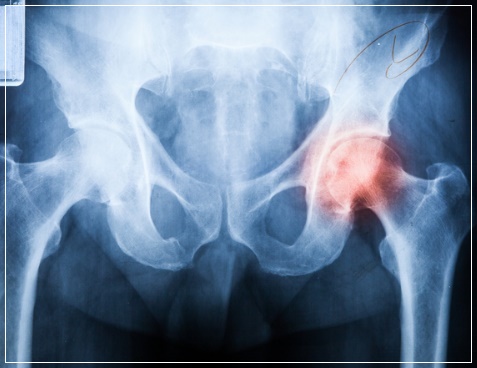

고관절은 골반과 허벅지 뼈를 이어주는 관절로 엉덩이 관절이라고도 불리며 우리 몸의 상체와 다리를 연결해 주는 대퇴골에 위치해 골반과 넓적다리뼈가 연결되는 관절입니다. 이 부분은 우리 몸을 지탱하며 하반신의 움직임에 결정적인역할을 하는 중요한 신체 부위입니다.

고관절 통증은 대게 나타나지 않다가 병이 상당히 진행된 다음에야 갑자기 시작되는 경우가 대부분이며 발을 땅에 디딜 때 심해져서 절뚝거리며 걷게 되고 양반다리와 같은 특정한 자세를 취할 때 통증을 느끼게됩니다. 엉치 쪽에 통증이 지속하거나사타구니, 무릎위쪽부터 골반 아래쪽까지 통증이 있을 때 보행 중에 통증 때문에 절뚝거리는 등 지장이 생기고 다리가 잘 펴지지 않으면 고관절 질환을 의심해 보아야합니다.

고관절 통증은 통증 자체로 보면 자칫 허리 디스크 질환과 혼동될 수도 있는데 그 이유는 고관절 자체가 다른 부위와는 달리 신체의 깊숙한곳에 있는데다 통증 부위 또한 정확하지 않기 때문입니다. 갑작스럽게 통증이 찾아오기 때문에 대수롭지 않게 여기고 넘겨서 병을 키우는 경우가 많습니다. 특히 이미 퇴행성 진행이 되고 있는 환자의 경우 방치하면 퇴행성 고관절염으로 악화될 수 있습니다.